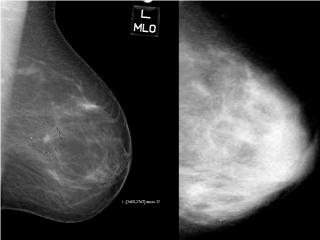

- Did you know that dense breast tissue is comprised of less fat and more connective tissue which appears white on a mammogram. Cancer also appears white thus tumors are often hidden or masked by the dense tissue. As a woman ages, her breasts usually become more fatty. However, 2/3 of pre-menopausal and 1/4 of post menopausal women (40%) have dense breast tissue. Additionally, as the density of the breast increases, the risk of breast cancer also increases.